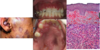

The wall of which cyst?

Periapical Cyst

Open clear areas = Cholesterol clefts where fat

used to be. Multinucleated cells (purple dots)

trying to break down cholesterol

What is this and what is it associated with?

keratin pearl – can be associated w/SCC